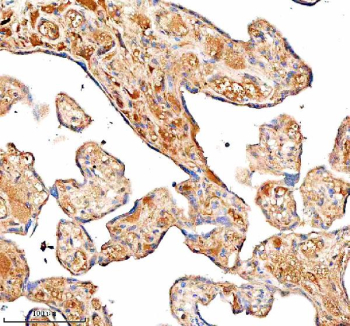

Immunohistochemical staining of SERPING1/C1 using anti-C1 Inhibitor (C1-INH) antibody. SERPING1/C1 was detected in a paraffin-embedded section of human placenta tissue. Heat mediated antigen retrieval was performed in EDTA buffer (pH 8.0, epitope retrieval solution). The tissue section was blocked with 10% goat serum. The tissue section was then incubated with 1:100 rabbit anti-C1 Inhibitor (C1-INH) antibody overnight at 4oC. Peroxidase Conjugated Goat Anti-rabbit IgG was used as secondary antibody and incubated for 30 minutes at 37oC. The tissue section was developed using an HRP secondary and DAB substrate.